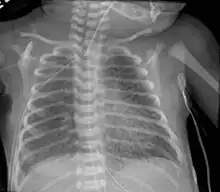

Pulmonary interstitial emphysema is the condition of air escaping overdistended alveoli into the pulmonary interstitium. It is a rare disease that occurs most often in premature infants, even though it is possible to appear in adults.[25] It often presents as a slow deterioration with the need for increased ventilatory support. Chest x-ray is the standard for diagnosis where it is seen as linear or cystic translucencies extending to the edges of the lungs.[9]